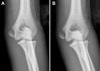

X-ray : 내상과 골절(medial epicondyle fracture), stable